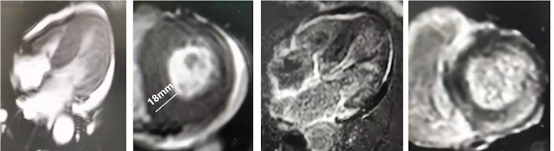

患者心脏MRI平扫+增强提示左室壁增厚,以室间隔为主,下间隔近段18 mm,下侧壁近段14 mm,双心室心肌广泛异常强化。初步考虑系统性淀粉样变性可能性大,心脏受累可能性大,心包积液、心律失常,心功能NYHA Ⅳ级,胃肠道受累可能(回肠溃疡),冠状动脉肌桥,轻度贫血,低T3综合征。

超声心动图检查左房25 mm,左室32 mm,右室15 mm,TIPS正常,EF 68%,左室壁增厚(室间隔及后壁15毫米,右室壁6毫米),心肌呈颗粒样回声,各房室腔内径偏小,左室舒张功能减低,少量心包积液。